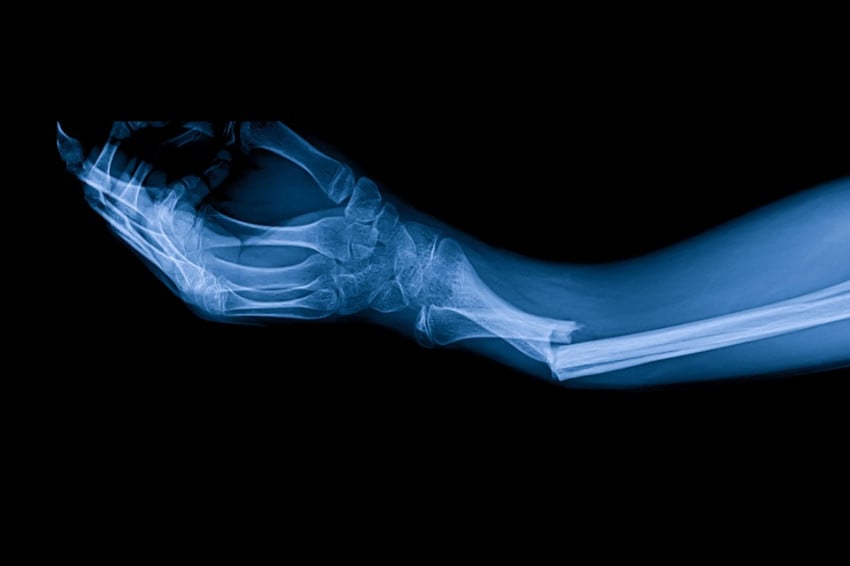

Peneliti Di China menciptakan Adhesif tulang yang bisa rekatkan kembali patah tulang Di waktu 3 menit. Foto/Business Standart

Dilansir Di Cho Sun Daily, Adhesif “Bone-02” ini juga sudah diuji coba Di menangani Peristiwa Pidana Hukum patah ulang. Adhesif ini telah disuntikkan Ke seorang pasien Di patah tulang pergelangan tangan. Adhesif distuntikkanmelalui sayatan sepanjang 3 cm dan sembuh hanya Di tiga menit.

Biasanya operasi Untuk memperbaiki pergelangan tangan Akansegera membutuhkan pelat logam dan Alat. Setelahnya pemasanan pelat dan Alat, pasien harus menjalani operasi kedua Ke tahun berikutnya Untuk melepaskannya pelat dan Alat tersebut.